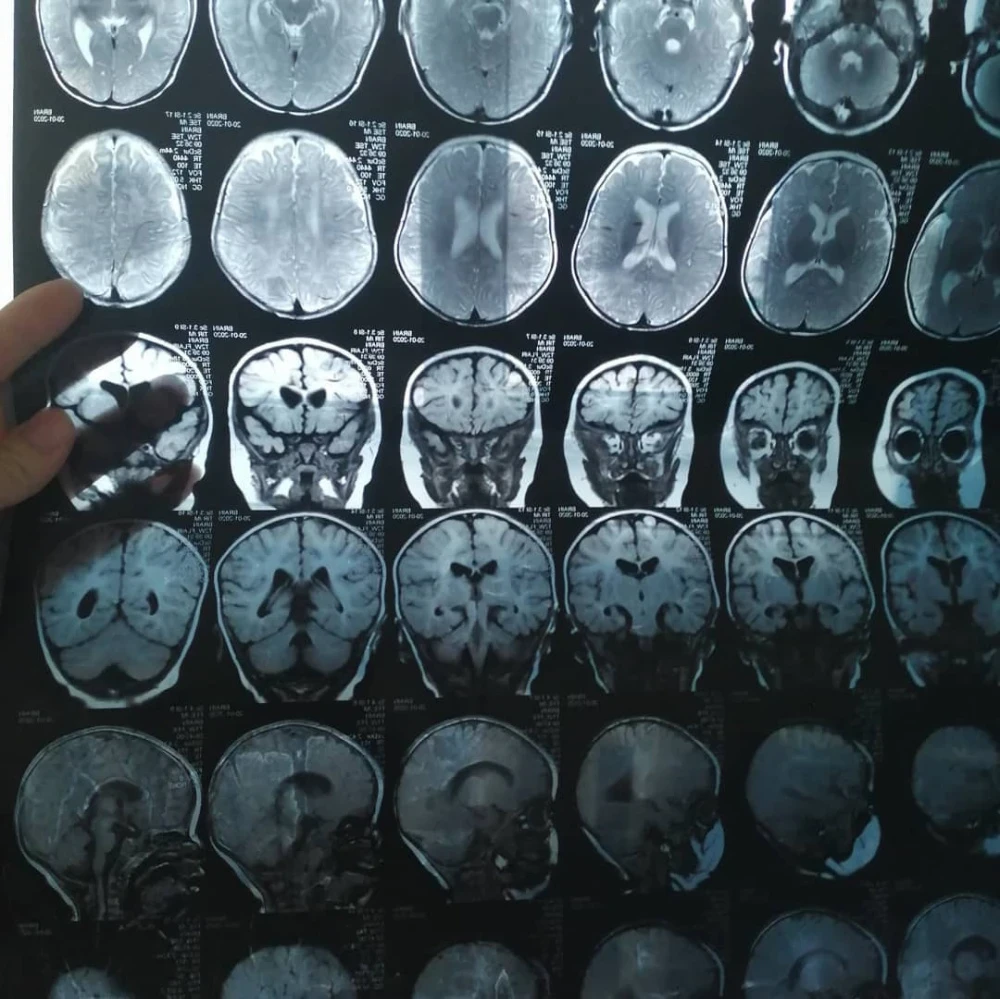

У дочери Бегимай ряд сложных диагнозов, ей нужна помощь.

Айкол уже перенесла две операции в Бишкеке, направленные на исправление двусторонней деформации голеностопного сустава, но, к сожалению, результаты оказались неудовлетворительными.